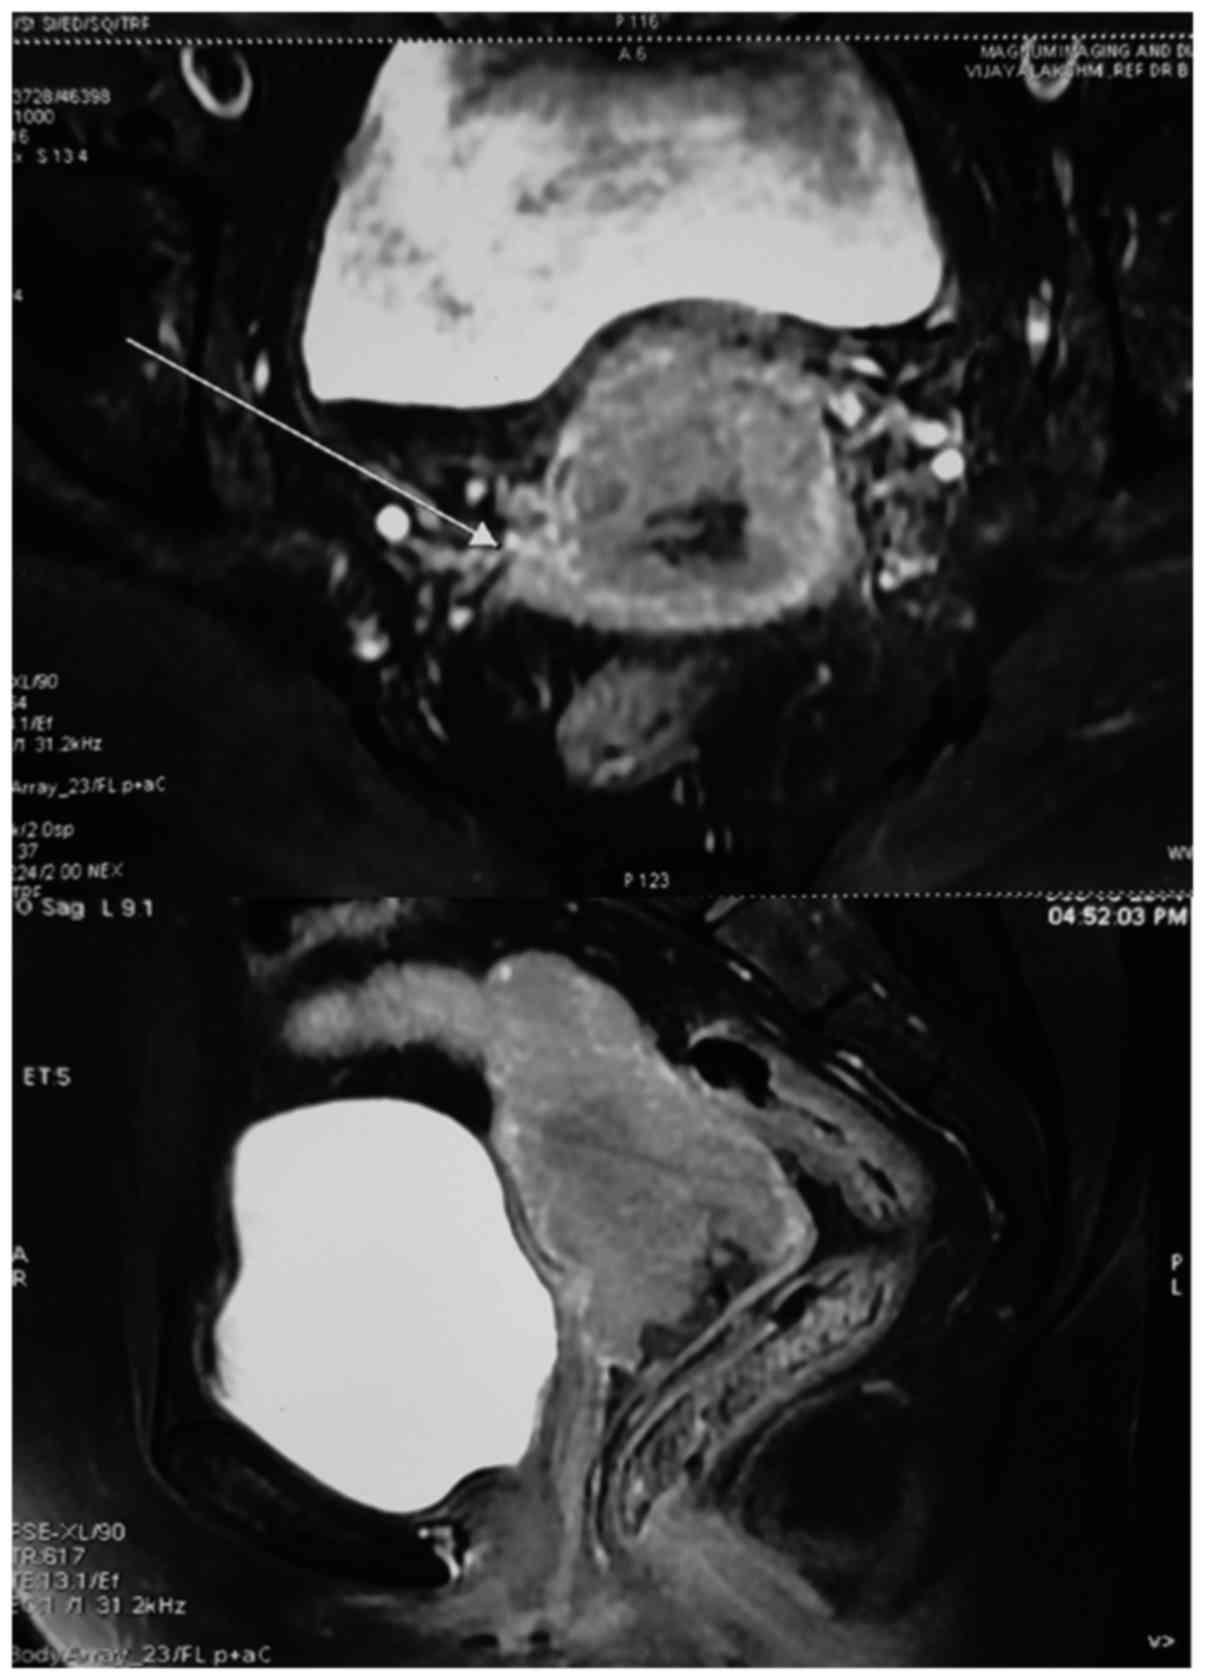

Her past medical history included type 2 diabetes and she was taking combination tablet of glimepiride 1 mg and metformin 500 mg twice daily for 3 years. Histopathological examination of the cervical biopsy specimen revealed moderately differentiated squamous cell carcinoma. The magnetic resonance imaging (MRI) of pelvis revealed a large mass of 55×45 mm in size in the uterine cervix infiltrating the lower third of the myometrium with enlarged bilateral internal iliac nodes, measuring 1.6 cm on the left side and 1.4 cm on the right side (Fig. 1). Based on these findings, the patient was diagnosed with squamous cell carcinoma cervix Stage IIIB, with Eastern Cooperation Oncology Group (ECOG) score of 2 and was planned for concurrent chemoradiotherapy.

Figure 1.

Prechemotherapy MRI pelvis with contrast: Growth in the uterine cervix infiltrating the lower 3rd of myometrium and bilateral parametrium; with enlarged bilateral internal iliac nodes (arrow).